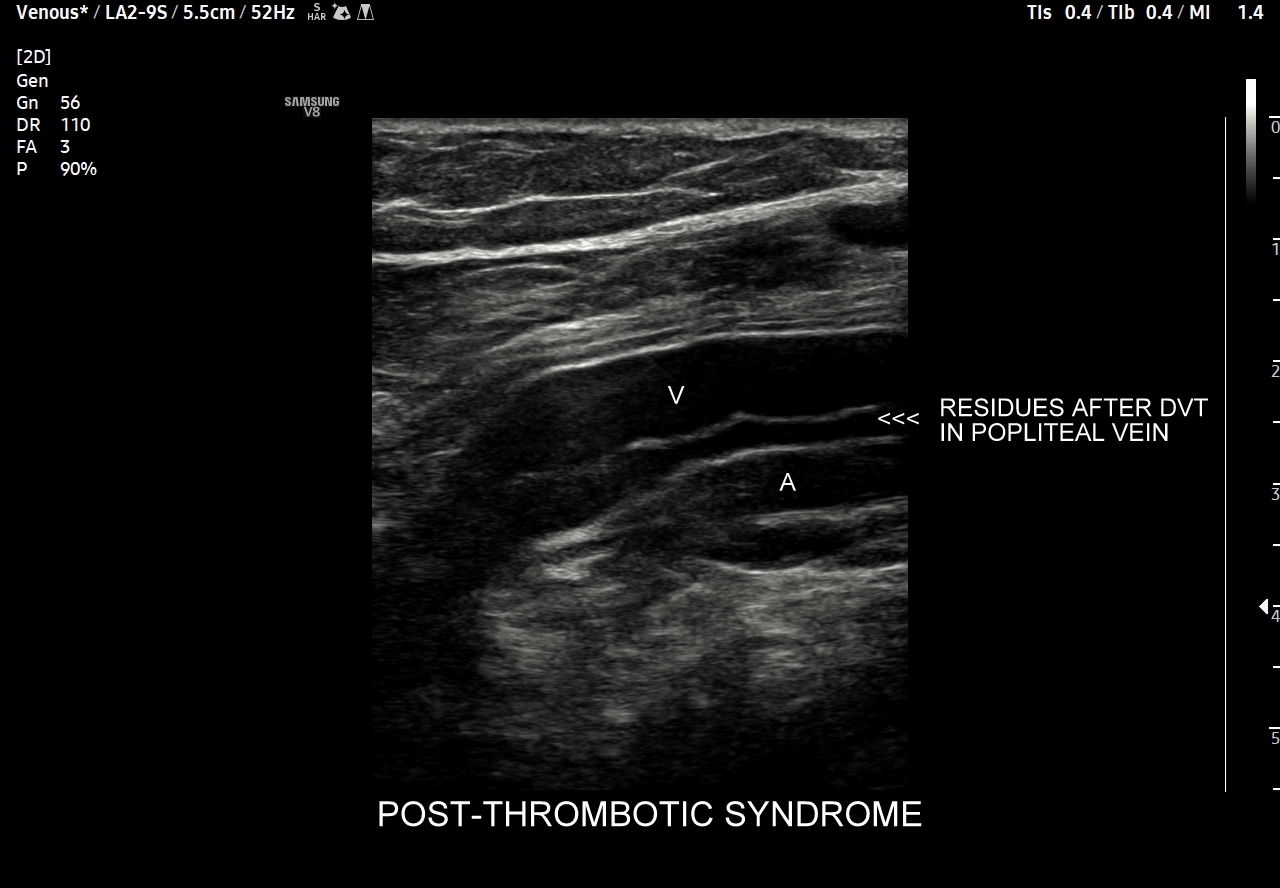

42. Patologie żył kończyn dolnych, w tym niewydolność żył powierzchownych i głębokich, żylaki, zakrzepica żył powierzchownych, zakrzepica żył głębokich, zespół pozakrzepowy.

Dzień żylny w ramach Kursu dedykowany jest dopplerowskiemu badaniu żył, w szczególności w obrębie kończyn dolnych. Otóż to właśnie w tym obszarze ujawniają się najczęściej choroby układu żylnego takie jak zakrzepica żył głębokich, zakrzepica żył powierzchownych, niewydolność żył powierzchownych i żylaki podudzi, niewydolność żył głębokich i zespół pozakrzepowy, które to badający lekarz powinien umieć rozpoznać. W trakcie interdyscyplinarnego Kurs USG Doppler Cedum ® omawiane są również hemodynamika krążenia żylnego w fizjologii i w stanach patologicznych; cele diagnostyczne, w tym planowanie zabiegów angiochirurgicznych i endowaskularnych w obrębie żył; a także nauczane są techniki funkcjonalnego badania żył kończyn dolnych i żył miednicy. Kurs obejmuje także tematykę dotycząca żyły głównej dolnej i jej brzusznych dopływów, żył szyjnych oraz żył kończyn górnych.